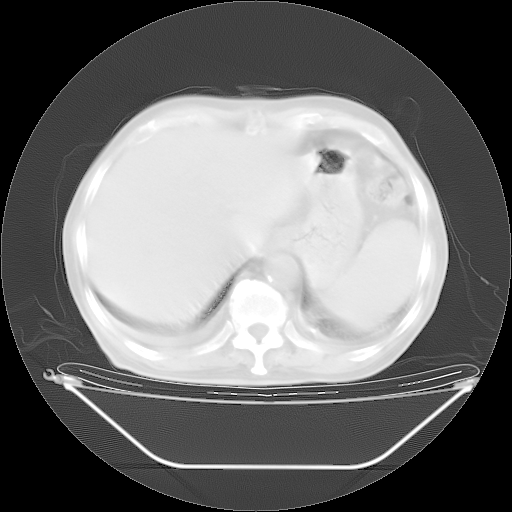

胸腹部CT,诊断意见:左上肺叶钙化灶、左侧胸膜局限性增厚并钙化、胆囊炎。描述部分肺组织呈磨玻璃样改变。

今天复查肺部CT,发现双肺广泛磨玻璃样改变。所以我把3月19日和5月9日相隔50天的肺部CT上传。请大家会诊。

2009年3月19日肺部CT片。

2009年3月19日肺部CT

大致读了系列胸部CT:纵隔窗无明显异常,肺窗:从4、27至今:主要是双肺中下野外带可见毛玻璃样改变,目前处于急性肺泡炎阶段,至于原因考虑1、结替组织或胶原血管性疾病所致?2、恶性疾病如恶组在肺部所致的表现或细支气管肺泡癌?3、药物或其它原因如肺蛋白沉着症所致肺泡炎目前不太可能?总之,明天就去请我院的呼吸科、感染科、血液科和临免专家会诊哈。